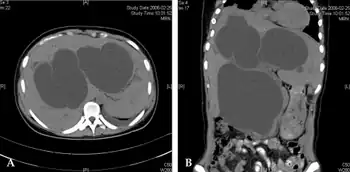

Diagnosis

.png.webp)

Direct hyperbilirubinemia